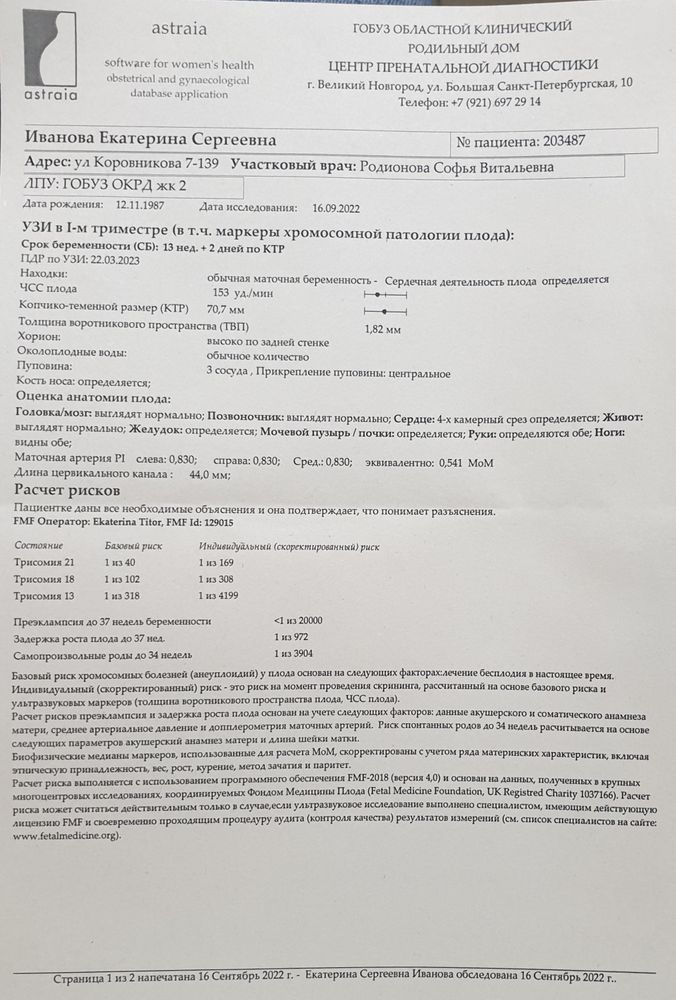

Первый скрининг

Что то переживаю...Узи делали в12,3. По размерам ктр 70 мм на 13,2 дн. Твп 1,8мм. А вот носовая кость 1,8мм очень смущает,маленькая... У кого нибудь было так же. Результаты крови надеюсь будут в понедельник. Не могу дождаться.